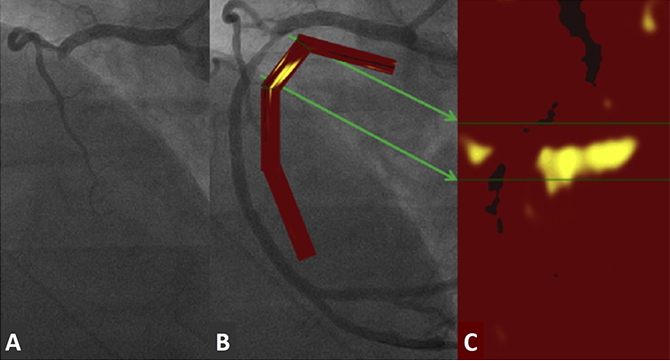

반면, 최근에 Joshi 등은 18F-sodium fluoride(18F-NaF)를 활용하여 급성 심근 경색 환자에서 PET-CT 분자영상 기법의 유용성을 보여주었다. 이 연구에서는 18F-NaF PET-CT를 이용하여 비침습적으로 경화반의 파열 및 culprit 병변을 정확하게 구분하였고 (그림 1), 18F-FDG PET-CT 기법에 비해 우월한 병변 구별 능력을 보여주었다. 향후 대규모 임상 연구 결과들이 뒷받침 된다면 매우 각광 받는 분자영상 기법 중에 하나가 될 것으로 기대된다.

그림 1. 비ST-분절상승 급성심근경색 환자의 18F-NaF PET/CT 영상. (A) 관상동맥 조영술 상 좌전하행 관상동맥(left anterior descending coronary artery, LAD)에 culprit 병변(빨간색 화살표)이 관찰되며, (B) 18F-NaF PET/CT 상 culprit 병변에서만 강한 분자영상 신호가 관찰된다.